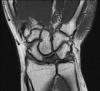

Kienböck hastalığının cerrahi dışında bilinen bir tedavisi yoktur. Ancak eğer hastalık çok erken evrede yakalanmış ve çekilen MRI görüntüleme sonrasında henüz osteonekrozun (kemik çürümesi) başlamadığı görülürse bir takım önlemler alınabilir. El bilek istirahat ortezi kullanılması, ödem giderici NSAID grubu ilaçların kullanılması ve yüksek basınçlı oksijen bunların arasında sayılabilir. Ancak bu şekilde takip edilen hastalarda sık olarak kontrol edilmeli ve tekrarlanan MRI görüntülemede osteonekrozun başladığı görülür ise cerrahi tedaviye geçilmelidir.